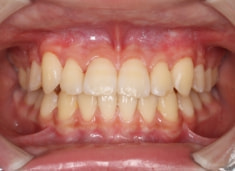

骨年齢は実年齢よりも低めなので、今後下顎の旺盛な成長が見込まれます。

検査時のレントゲン分析では、上下顎の関係は、上顎の劣成長があり下顎前突傾向という値がでておりましたが、前歯ジャンプ後はフェイスマスクの効果もあり、上下顎の関係は正常化しています。

上顎が若干優位になっていますので、今後の下顎の成長のための貯金になっているくらいです。